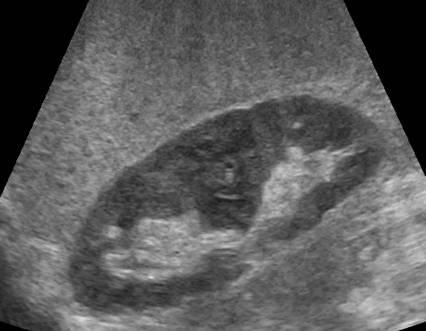

Pancreatic Psydocyst

Spherical fluid collection of pancreatic enzymes that arise from inflamatory, necrotic and hemorrhage processes of the pancrreas

persistently elevated amylase and lipase

Pancreatic Psydocyst

Spherical fluid collection of pancreatic enzymes that arise from inflamatory, necrotic and hemorrhage processes of the pancrreas

persistently elevated amylase and lipase

Pancreatic Psydocyst

Spherical fluid collection of pancreatic enzymes that arise from inflamatory, necrotic and hemorrhage processes of the pancrreas